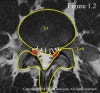

X-ray에서 비특이적인 퇴행성 변화가 보입니다. 4주 이상 지속되는 증상, 심각한 신경학적 증상이나 악화되는 신경학적 장애, 극심한 통증 시에는 병변 확인을 위하여 MRI를 촬영합니다.

MRI : 요추디스크 탈출(Lumbar Herniated Disk)